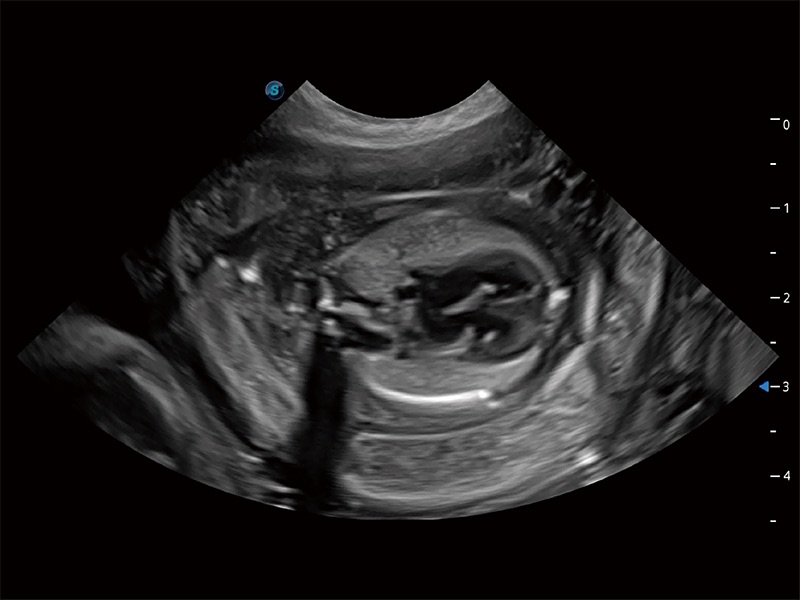

高性能和先进的临床应用工具可以为动物医生提供临床信心。ProPet 80 搭载了先进的腹部和浅表应用工具,帮助医生在日常临床实践中发挥前所未有的作用。

极大提升超低速微细血流的检出能力,同时更精准地滤除软组织和超声信号,为兽用医生提供以往无法通过常规血流获得的疾病诊断信息。

ProPet 80 专为动物医生设计,对不同的动物体型和生理结构作出了针对性的优化。通过动物影像专用软件,可满足个性化的应用需求,帮助动物医生获得更精确的诊断数据。

ProPet 80 全新的动物超声智能软件和丰富的探头群,为动物医生提供了高清晰度和精细分辨率的图像,无论在宠物、马科、畜牧还是实验室动物等应用中都可以轻松应对,为您的日常工作带来满意的体验。